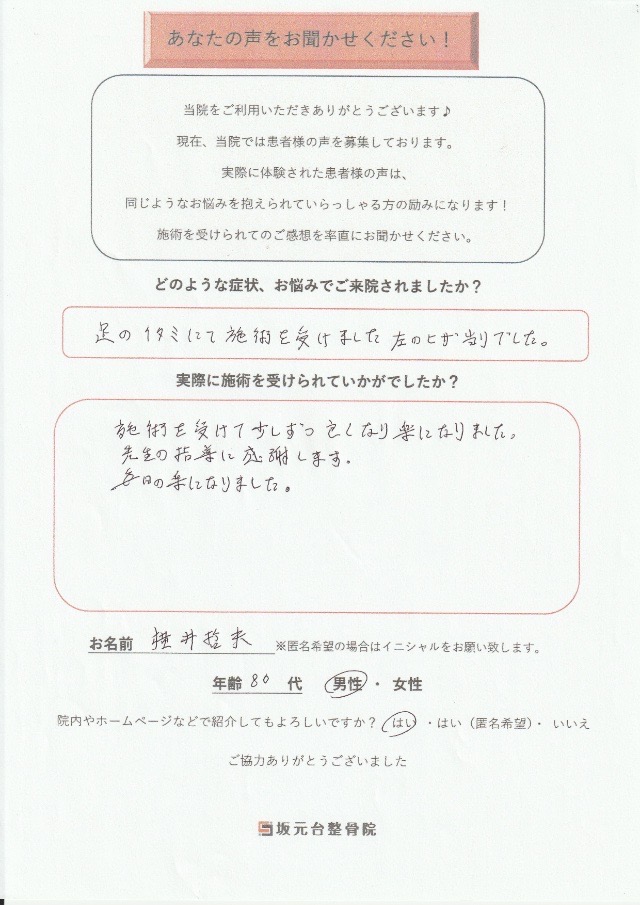

左膝の痛みにお悩みだった80代男性患者様の声

お名前 横井哲夫さん 年齢80代

施術期間7週間 施術回数6回

どのような症状、お悩みでご来院されましたか?

足のイタミにて施術を受けました。左のヒザあたりでした。

実際に施術を受けられていかがでしたか?

施術を受けて少しずつ良くなり楽になりました。

先生の指導に感謝します。

毎日楽になりました。

・初診時は足を引きずりながら苦痛にゆがんだ表情を浮かべておりましたが、今は笑顔でお話ししているお姿を見れて、私としても嬉しく思います。

・現在は1ヶ月に1回のメンテナンス通院をすることにより、良い状態を維持できています。